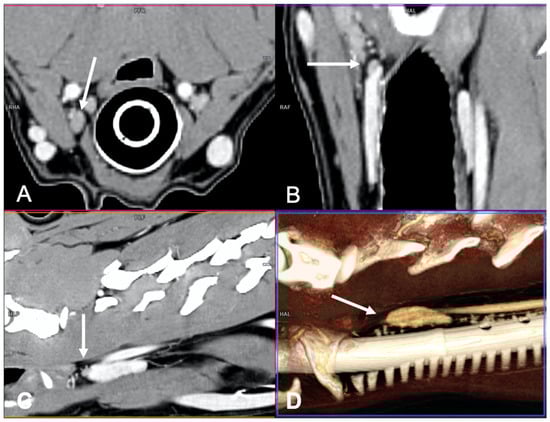

The adenomas were mainly ovoid in shape (58%) and with homogeneous enhancement (67%) (Figure 3).

Figure 3.

CT appearance of parathyroid gland adenoma. Post-contrast dorsal CT reconstruction in two dogs with parathyroid gland adenoma (arrow) at the level of the right external parathyroid. Note the rounded (A) and ovoid (B) shape; in both cases the parathyroid adenoma is hypoattenuating with respect to the thyroid tissue and homogenously enhancing.

The adenocarcinomas (Figure 4) showed variable shape and enhancement, with half of the cases showing homogeneous enhancement and half showing heterogeneous enhancement after contrast administration.

Figure 4.

CT appearance of parathyroid gland adenocarcinoma. Post-contrast dorsal CT reconstruction in two dogs with parathyroid gland adenocarcinoma (arrow) at the level of the left external parathyroid. Note the variable CT appearance: large size of the lesion in (A) showing heterogeneous contrast enhancement; the adenocarcinoma in (B) is smaller, has a rounded shape, and homogeneous contrast enhancement.